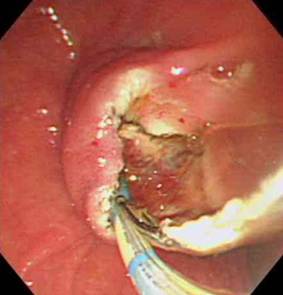

둘째는 삽관된 카테터로 방사선 조영제를 주입하여 담관 또는 췌관에 대해 방사선 투시 및 촬영을 하여 진단을 하고 필요하면 유두부를 절개하여 담관-췌관의 병을 치료하는 것이다. 이런 시술을 내시경 역행성 담도-췌관 조영술(ERCP)이라고 한다. 즉, 이 검사는 내시경 검사와 방사선 검사 둘 다를 포함한다. 따라서 ERCP를 시술하는 의사는 내시경 술기와 투시 조영술 모두에 전문가이어야 한다. 또한 ERCP를 이용한 중재적 시술은 상부소화관내시경 검사보다 시간이 더 걸리고 중증의 합병증 위험이 있어서 모든 내시경의사가 ERCP를 할 수는 없고 전문적인 수련 과정을 이수한 후에 시술을 하는 것이 바람직하다.

ㆍ담관 결석의 제거

ㆍ담관염의 치료를 위한 담즙액의 배액